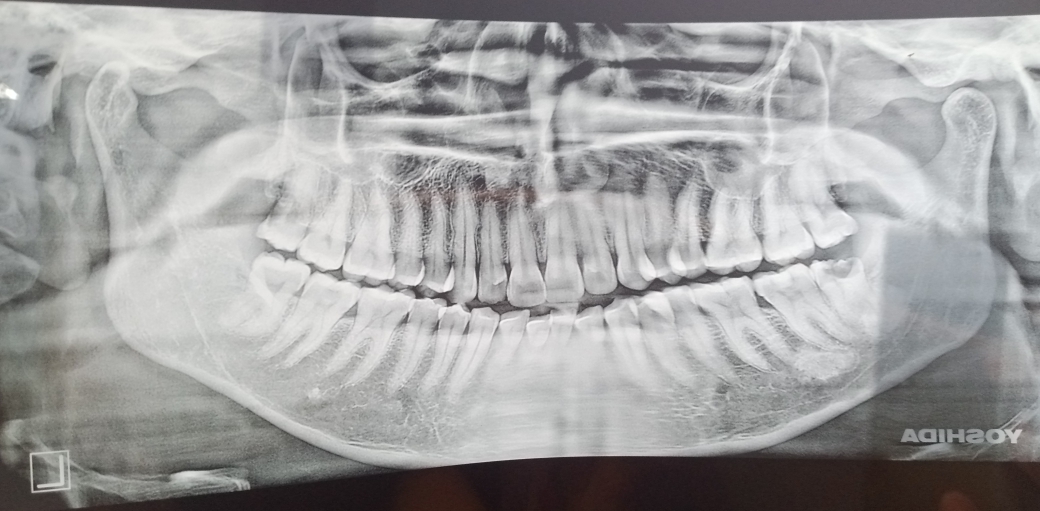

میری عقل دارٹھ آدھی سے زیادہ ختم ہو چکی ہےساتھ چھوٹا سیسٹ ہے۔ایکسرے دیکھ کے بتا سکتے ہیں کہ اسکو نکلوانے پہ کتنی فیس یا اپریٹینگ چارجز کتنے ہونگے۔

this wisdom needs extraction. charges 12 thousand

Wisdom Extraction 8,000